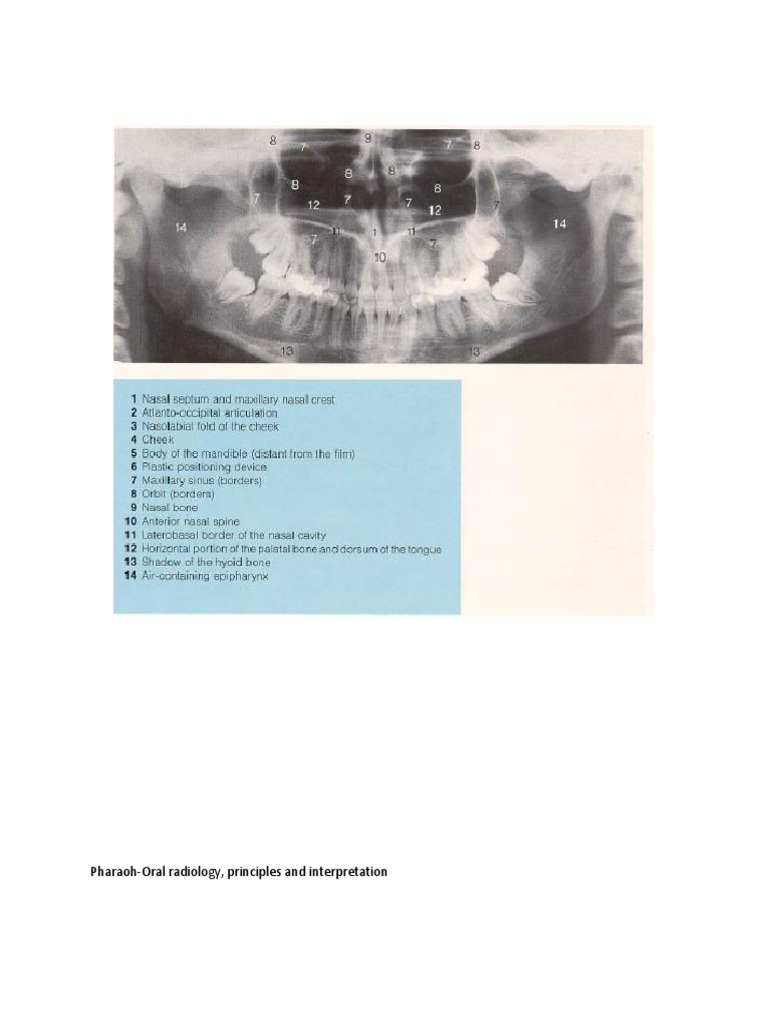

PharaohOral Radiology, Principles and Interpretation PDF Oral Radiology Principles And Interpretation Pdf Principles and interpretation, 7th edition visually demonstrates the basic principles of oral and. Principles and interpretation, 7th edition visually. Principles and interpretation, 7th edition visually. Written specifically for dentists, white and pharoah’s oral radiology: Principles and interpretation, 7th edition. Oral Radiology Principles And Interpretation Pdf.